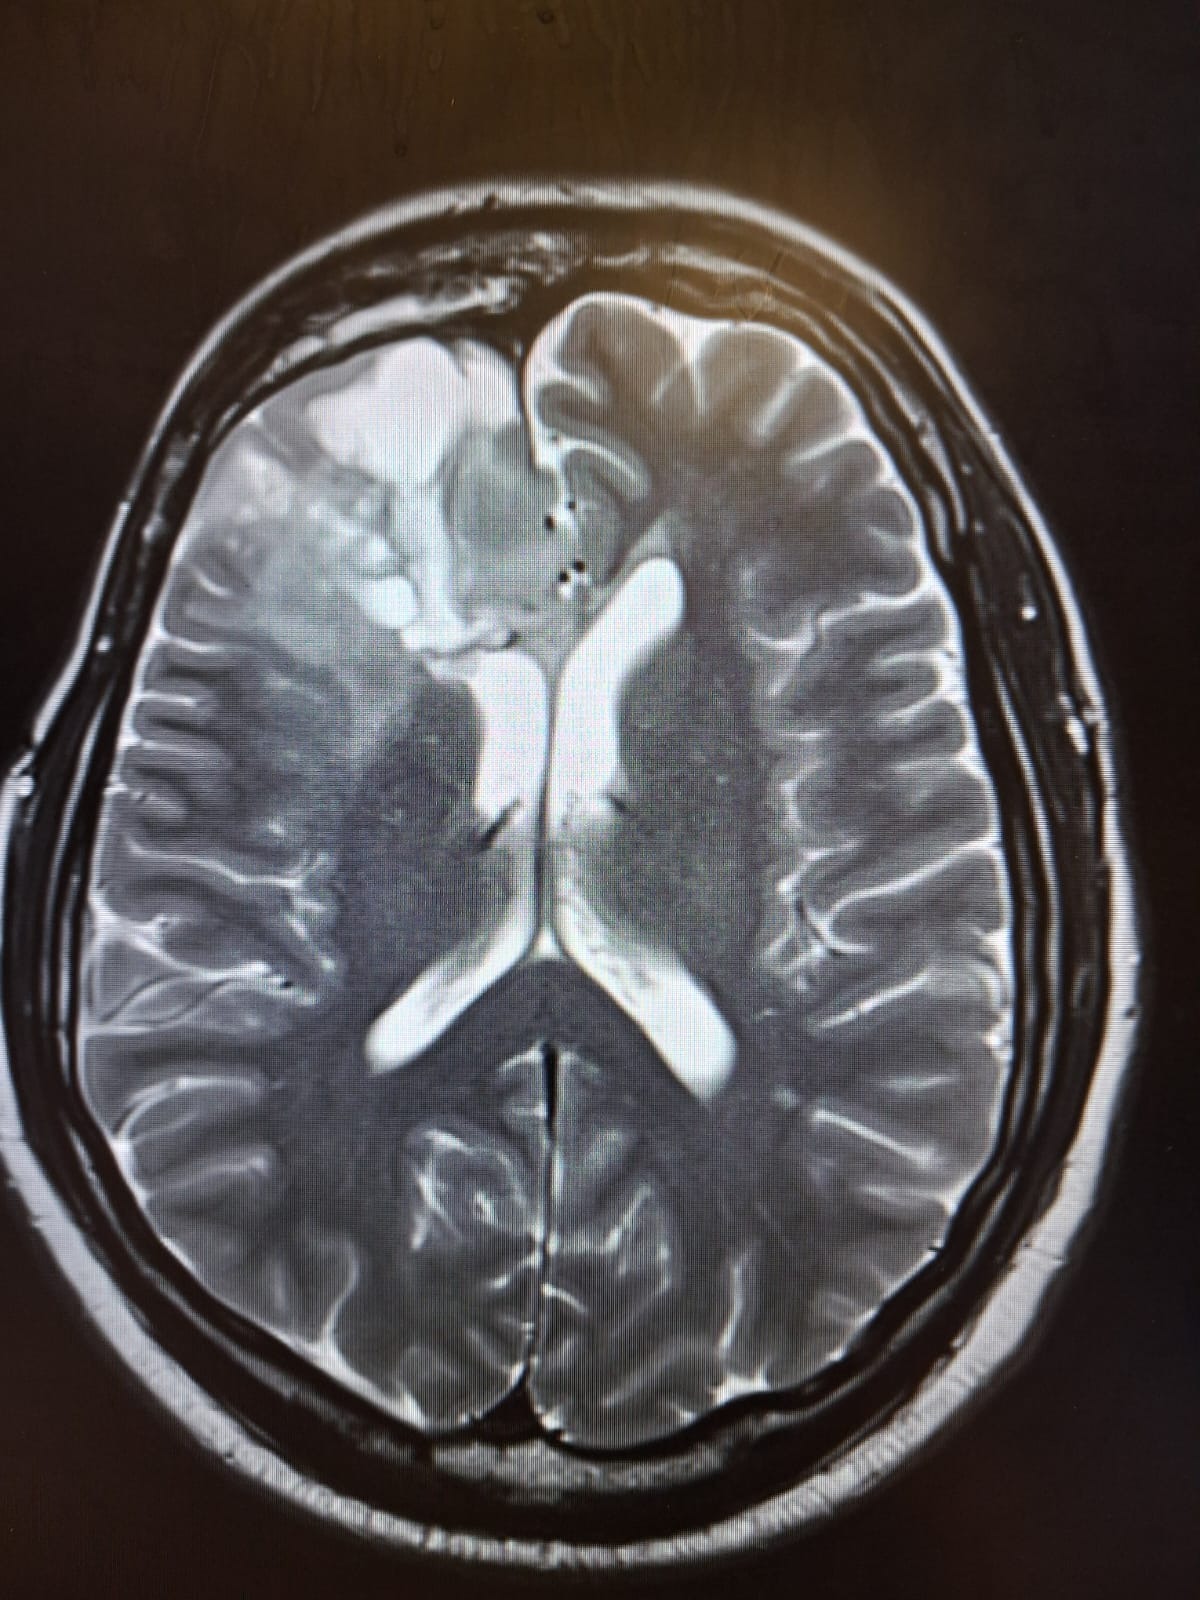

To give you a small back story 17 years ago after having a seizure the doctors found a grade 3 right frontal lobe anaplastic astrocytoma. He was given major brain surgery followed by intensive radiotherapy. After the fight of his life he was given a survival rate of 5 years. He surpassed that by an extra 12 year. He was incredibly lucky.

Then in December 2025 he started getting headaches again, after a scan it revealed the cancer was back and worse than ever, it is bigger and has progressed into grade 4. Alot of treatments are not available for him, it is inoperable, radiotherapy can not be done again. Leaving us with only the option of chemotherapy, even with this they can only give us around a year. We are devastated.